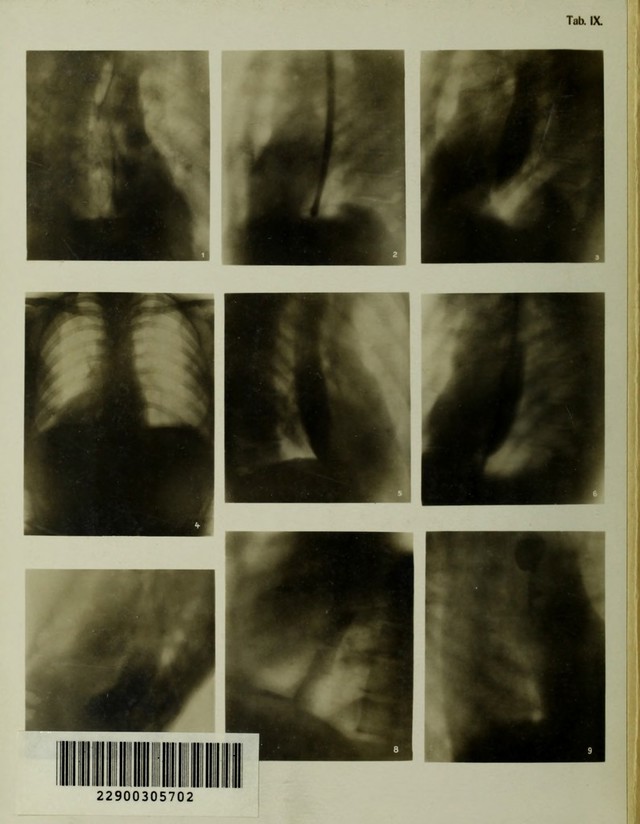

Atlas typischer Röntgenbilder vom normalen Menschen : ausgewählt und erklärt nach chirurgisch-praktischen Gesichtspunkten, mit Berücksichtigung der Varietäten und Fehlerquellen, sowie der Aufnahmetechnik / von Rudolf Grashey.

Credit: Atlas typischer Röntgenbilder vom normalen Menschen : ausgewählt und erklärt nach chirurgisch-praktischen Gesichtspunkten, mit Berücksichtigung der Varietäten und Fehlerquellen, sowie der Aufnahmetechnik / von Rudolf Grashey. Source: Wellcome Collection.